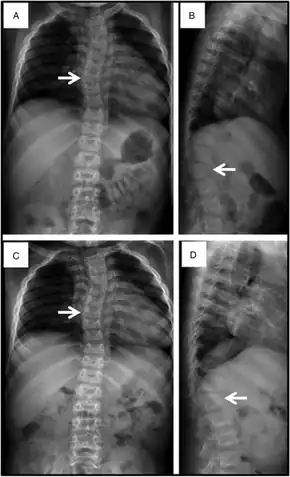

The most severe cases of Sly syndrome can result in hydrops fetalis, which results in fetal death or death soon after birth. Some people with Sly syndrome may begin to have symptoms in early childhood. Symptoms can include an enlarged head, fluid buildup in the brain, coarse facial features, enlarged tongue, enlarged liver, enlarged spleen, problems with the heart valves, and abdominal hernias. People with Sly syndrome may also suffer from sleep apnea, frequent lung infections, and problems with vision secondary to cloudy corneas. Sly syndrome causes various musculoskeletal abnormalities that worsen with age. These can include short stature, joint deformities, dysostosis multiplex, spinal stenosis, and carpal tunnel syndrome.[1]